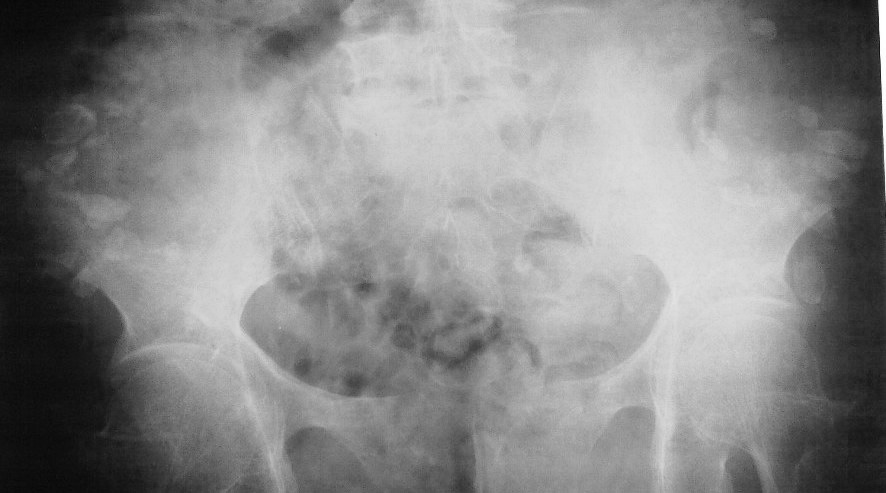

髂翼下方对称性多发钙化灶 是什么病?

双侧髂翼重叠处可见对称性多发钙化灶,部分位于髂骨影外;

考虑肌内注射所致钙化灶。

不光是髂翼下方对称性多发钙化灶,骶髂关节前方好象也有少量。可定为软组织内钙化影,与髂骨无关。

应该是个老年患者,以前医疗条件不好,用药需要肌肉注射。。考虑医源性软组织钙化。

今天问病人了,说的是打针造成的,,透视位于上后方  可以证实//谢谢各位的帮助,,